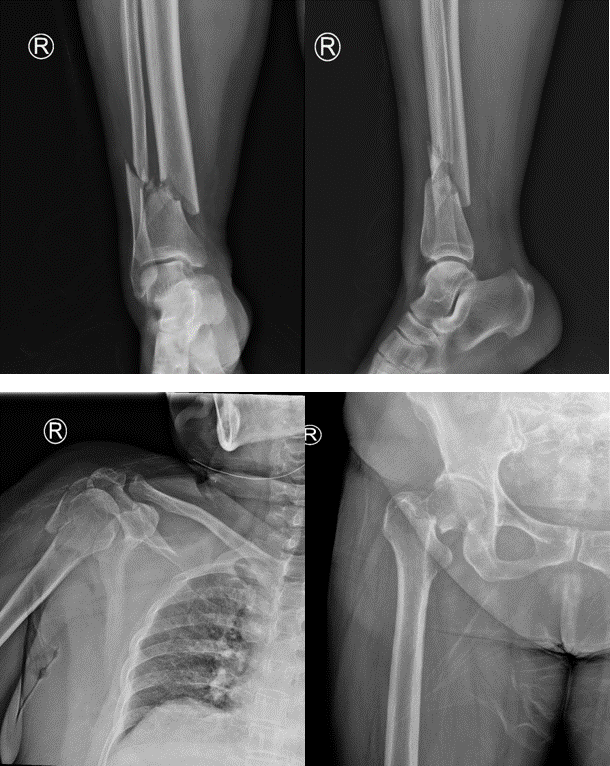

老家安徽的陈女士在苏州工业园区已经生活了很多年,一年前不幸遭遇车祸,当时短暂昏迷,全身疼痛无法活动,右侧耳还伴有出血。送至我院急诊后,诊断为:脑挫裂伤、肺挫伤、颅骨骨折、右侧上下肢骨折、右侧多根肋骨骨折,遂将患者收住重症监护室进行抢救治疗。

骨折X线